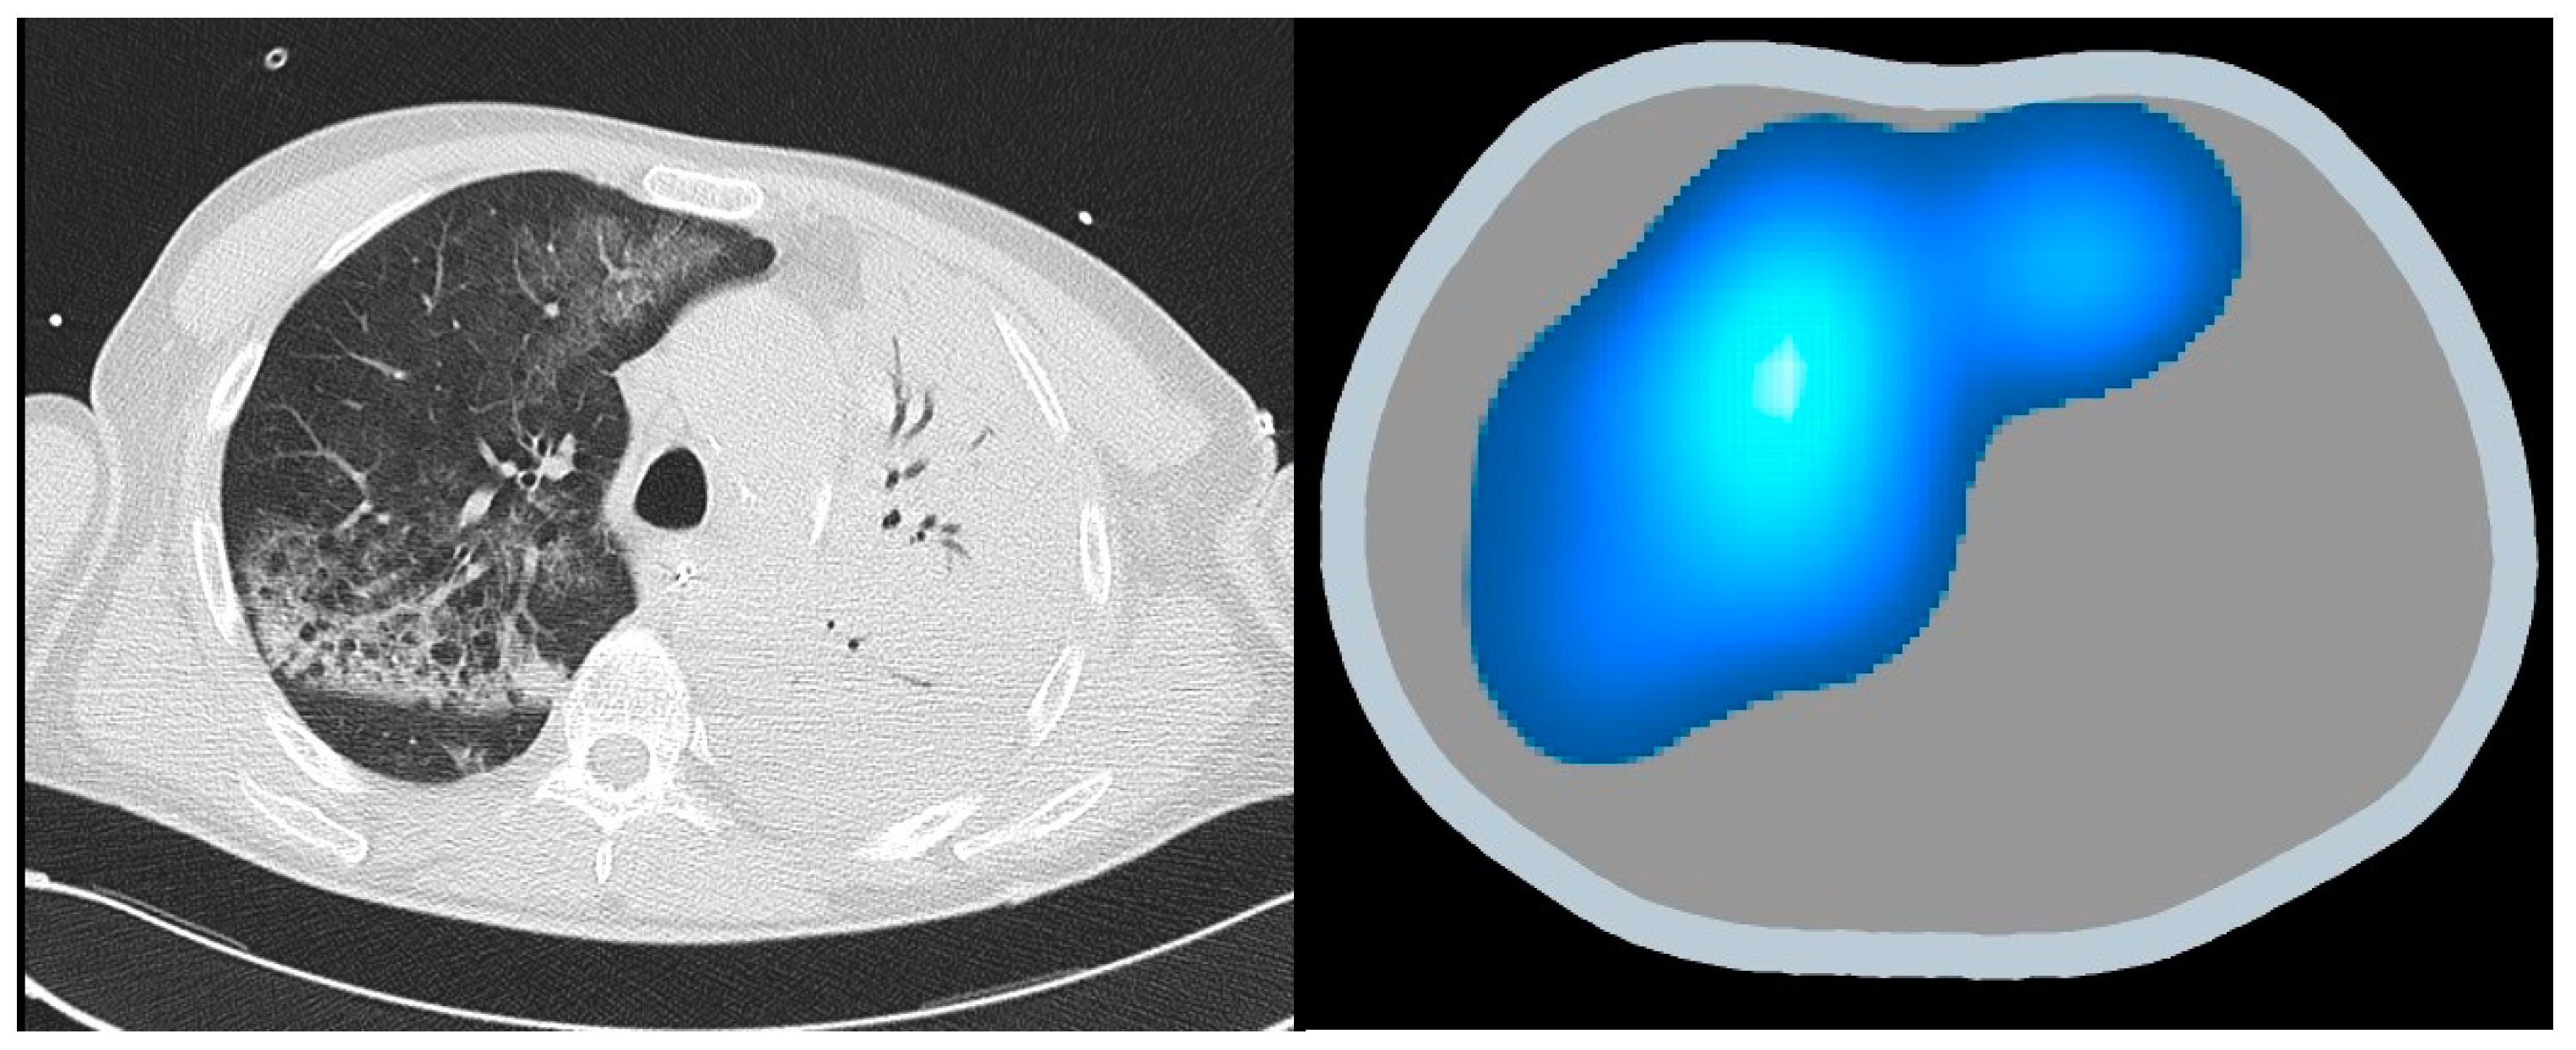

The incorporation of EIT within the schema of ARDS management heralds a paradigmatic shift toward a more individualized, data-driven ethos of care. This integration not only fosters a more profound comprehension of the pathophysiology underpinning ARDS, but also augments the avenue for personalized therapeutic stratagems. The confluence of EIT’s real-time visualization and the data-driven insights it engenders marks a new era in the quest for a more refined and effective management of ARDS. Through the lens of EIT, the veil shrouding pulmonary inhomogeneities in ARDS is gradually lifted, thus offering a clearer sight for tailored therapeutic interventions (Figure 6).

Figure 6. Revealing lung inhomogeneities in ARDS: comparing CT scan with EIT.